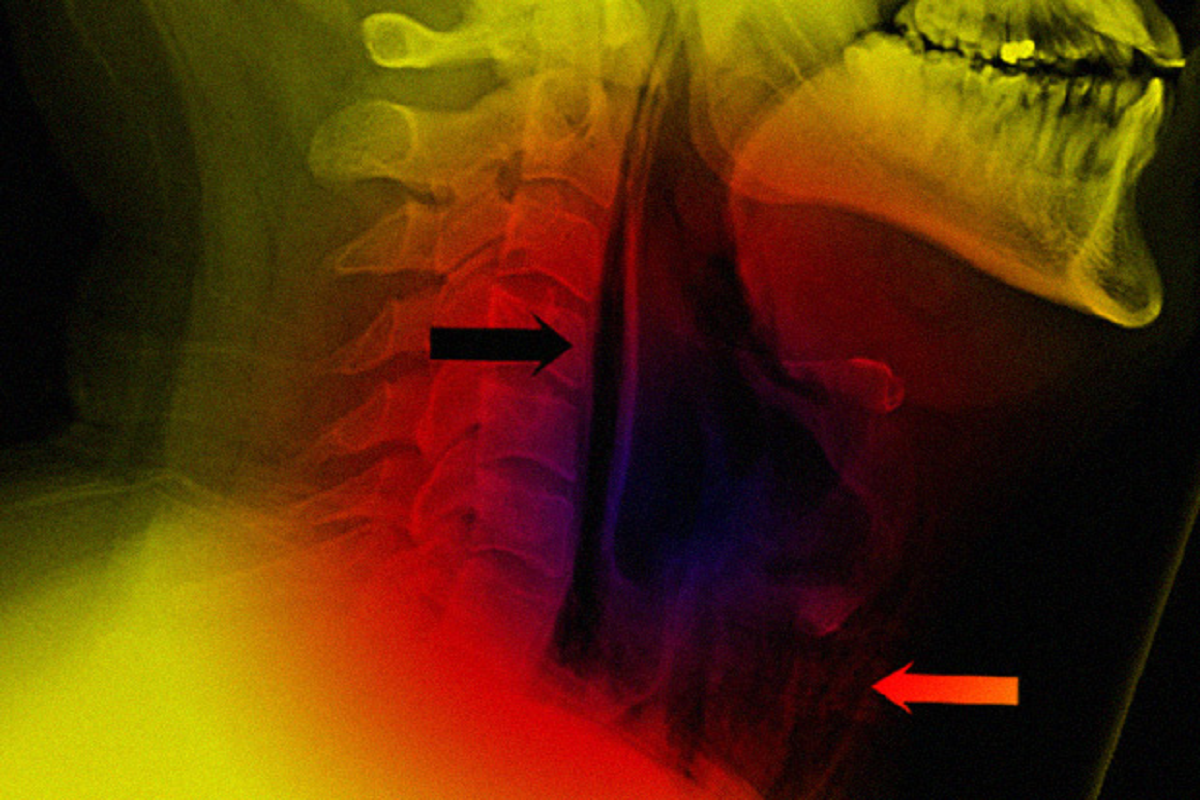

В ЦРБ города Суоярви в Карелии рассказали о случае, когда попытка чихнуть с зажатым носом стала причиной обращения пациента к врачу. Мужчине разорвало глотку.

Неприятность случилась с 34-летним мужчиной. Он обратился в больницу с жалобами на острую боль при глотании и изменение голоса. По словам пациента, симптомы появились после того, как он попытался остановить чих, зажав нос и рот руками. Остановить рефлекс не получилось, но после он заметил, как опухла шея.

Рентген снимок показал, что у мужчины спонтанный разрыв пищевода.